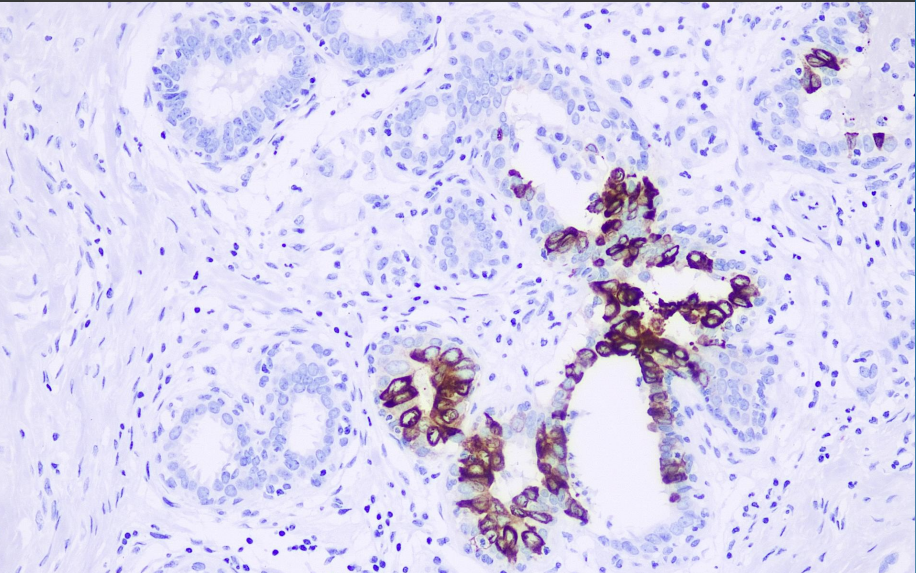

Positive control: mammary gland

Mammary globulin is a mammary gland associated glycoprotein and is a distant relative of the secretin family, which includes uterine globulin and lipophilin. Unlike other members of the secretin family, the mRNA of mammary globulin is specifically expressed in breast tissue. Studies have shown that this protein is a sensitive reference for studying latent breast cancer cells in sentinel lymph nodes and peripheral blood. In the detection of paraffin tissue sections, the sensitivity of this antibody in detecting mammary globulin in breast cancer tissues is as high as 80%. When used in combination with other mammary specific references such as GCDFP-15, the sensitivity for detecting mammary globulin can reach up to 84%. Detection of mammary globulin plays a crucial role in studying whether primary cancer has metastasized.

The Mammaglobin antibody reagent can specifically bind to the Mammaglobin antigen. The immunohistochemical kit containing the Mammaglobin antibody reagent is suitable for the precise diagnosis of breast cancer.